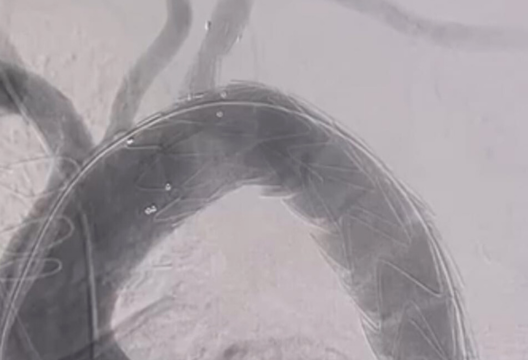

However, an effective and safe solution exists and is being actively implemented in many clinics around the world. Specialists of the Heart Center UMC, following the best practices, for the first time among the CIS and Central Asia countries adapted a new technology for minimally invasive implantation of the Castor graft. This stent graft consists of a metal frame coated with a special polymer that strengthens the weakened aortic wall. The uniqueness of the stent lies in its design, in which the aortic body and the outgoing lateral branch are stitched and opened together during implantation. The position of the stent and its branches is fixed and adapted to the anatomical features of the patient, so as not to disrupt the blood supply to the upper extremities.

The team successfully implanted the Castor stent graft in a clinic’s patient diagnosed with a chronic thoracic aortic aneurysm with dissection. The diagnosis was complicated by concomitant diseases and high blood pressure. Before the procedure, the patient experienced chest pains, shortness of breath, and weakness.

“The new technology differs in its design in that it has a lateral branch for simultaneous prosthetics of the subclavian artery. Previously, we made special holes when implanted stent grafts so as not to block blood flow, and the procedure took longer. This stent allows implantation to be performed much faster, more efficiently and safer,” shared Marat Aripov, Director of CAD for Interventional Cardiology and Radiology at the UMC.